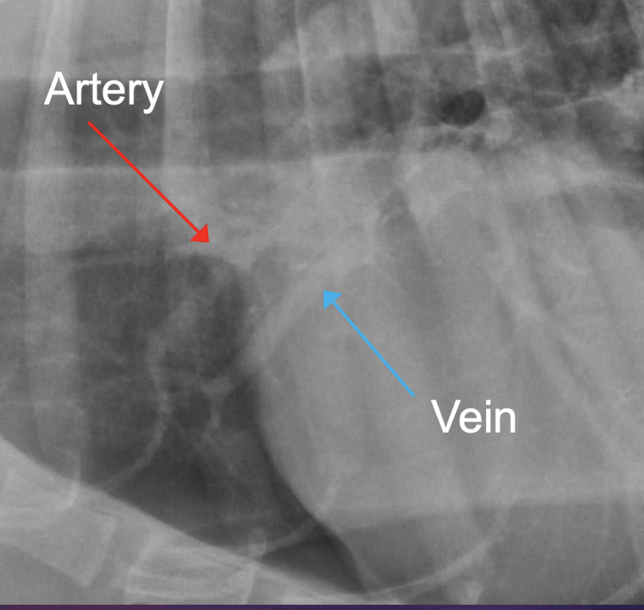

Q

Pulmonary vessels

A

-artery(dorsal), bronchus(mid) and vein(ventral

-artery and vein should be equal in size

-compare vessels to diameter of the most proximal aspect of 4th rib

-artery and vein should have similar width and should have a width less than the 9th rib where they cross it